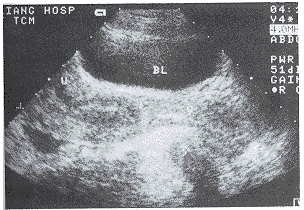

RC的超声诊断标准和分度的探讨:我们观察测量50例正常男女性仰卧位直肠声像图表现:在直肠肛管交界处前方可有1~10mm深的前突(图2),因此我们将≥10mm者列入异常统计。在临床治疗中,为了明确病变的严重程度,我们进行了分度的探讨。在观察中,我们发现症状严重者突出深度越深,而长度变短或变化不大,因此考虑以深度作为分度代表其严重程度。即前突深度10~20mm为轻度,21~30mm为中度,≥31mm为重度。本组轻度8例,中度13例(图3),重度3例(图4)。这种以深度为准的分度方法经临床观察、治疗是可行的。一般轻度者可采用中药治疗,中度以上可手术治疗,该分度法我们将在今后的工作中进一步研究探讨其可行性。

V:阴道,BL:膀胱,U:子宫 *:直肠前壁

图2 正常女性直肠前壁1~10mm突起